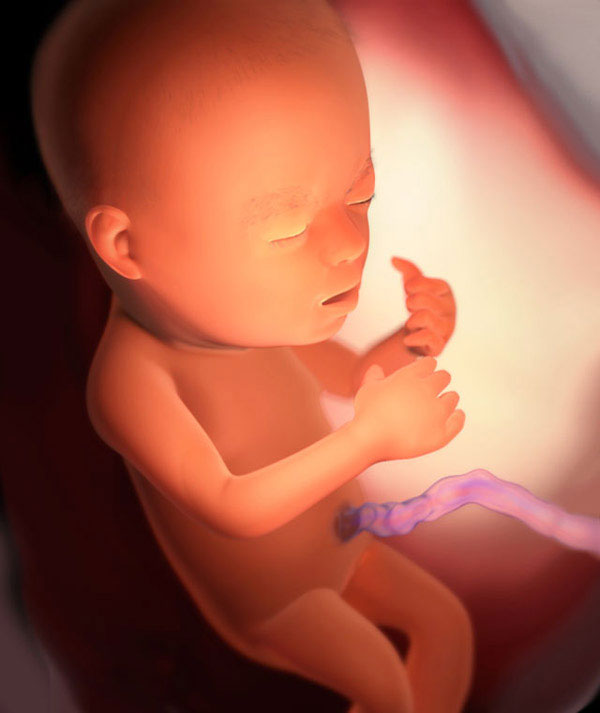

Et voici le fruit:

Le développement du fœtus:

- les ongles complètement formés commencent à se développer;

- les glandes sudoripares s'améliorent;

- le nombre de connexions neuronales augmente;

- dans un nez minuscule, un septum cartilagineux se forme;

- la minéralisation osseuse se poursuit;

- toutes les vertèbres et les disques intervertébraux sont entièrement développés dans la colonne vertébrale;

- le pancréas est complètement prêt pour le travail;

- les yeux du bébé ont déjà un iris, mais il n'a pas encore de pigment (c'est pourquoi les yeux changent de couleur chez les nouveau-nés).